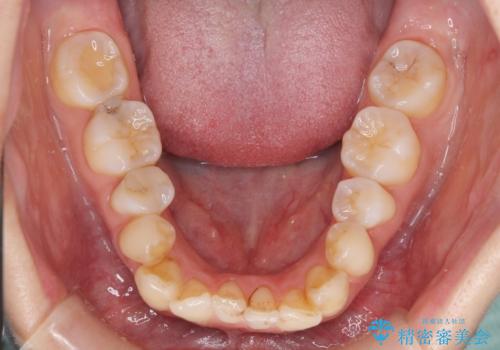

補助装置により上顎歯列を遠心移動させたため、非抜歯でしたが口元の突出感をある程度改善させることができました。

欠けてしまった前歯もオールセラミッククラウンにて自然に補綴することができました。